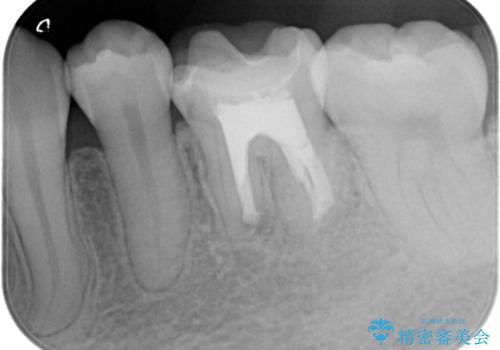

- 昔他院で根管治療を行った歯の病気が再発したことを主訴に来院されました。

レントゲンにて根尖に病変を認め、根尖性歯周炎の診断のもと以下の治療をご提案しました。

1、再根管治療を行い、3ヶ月以上経過を待ち、治癒しなければ外科的歯内療法を行う。

2、外科的歯内療法を行う。

以前の根管治療の質が不明なこと、補綴処置のやりかえにメリットがあることから、1の選択肢をお勧めしましたが、費用対効果の面を患者様と相談し今回は外科的歯内療法で治療することとしました。